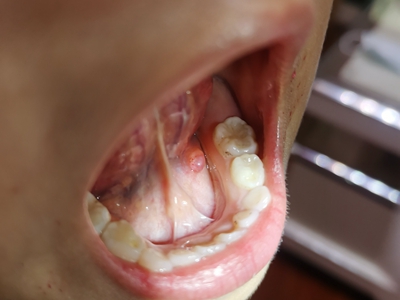

舌下腺囊肿舌头下面右侧有一个紫色包块图

舌下腺囊肿出现在口底舌系带一侧,表现为紫蓝色的隆起性包块,形态大致呈球形,界限清楚,质地柔软,囊肿增大后因破裂流出黏液。